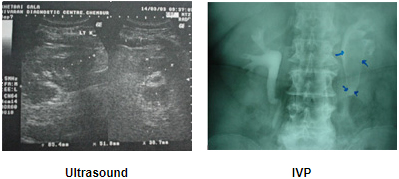

A 47-year-old gentleman presented history of dull pain in the right flank of 6-months duration. Ultrasonography showed evidence of multiple gallstones and a thick walled gall bladder and gross hydronephrosis of the right kidney. IVU showed delayed excretion and drainage of the contrast and classical sea-horse sign (reverse J) confirming retrocaval ureter. Cystoscopy with retrograde urography confirmed our diagnosis. A Zebra wire was placed, which easily bypass the obstruction. A ureteric catheter was advanced to just below the obstruction. In the right lateral position with a 70 degree tilt, the same 4 ports were used. Right colon was mobilized adequately; ureter and inferior vena cava was exposed. The dilated upper ureter was mobilized till it started to wind around the inferior vena cava. The upper ureter was transacted and the circumcaval segment was transposed anteriorly. Uretero-ureteral anastomosis was performed with 4-0 vicryl. There was same difficulty in placing a stent. Therefore ureteric catheter was placed over the Zebra wire in position. The operating time was 240 minutes. Blood loss was insignificant. Patient made speedy recovery and resumed normal activity after 10 days. At 3-months follow-up an IVU showed good drainage.